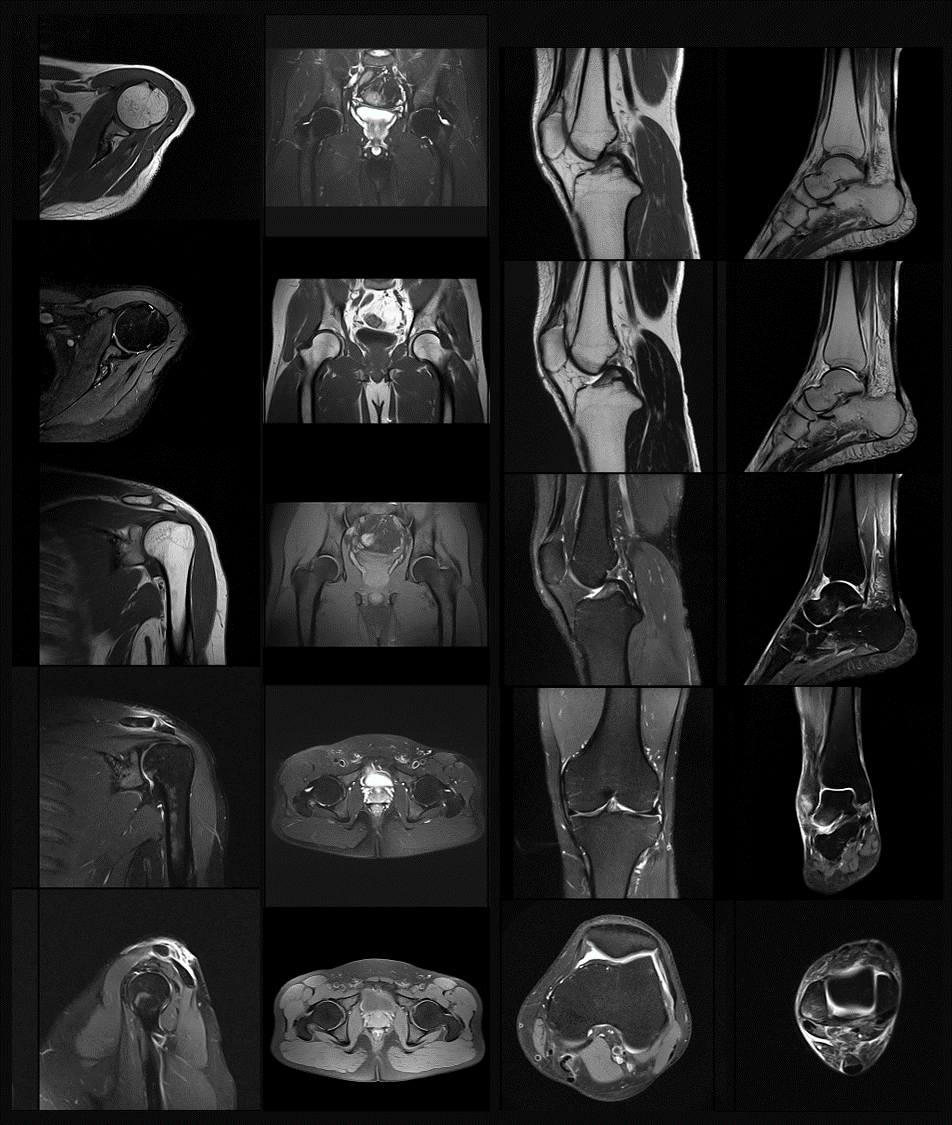

¹Ç¼¡ÏµÍ³